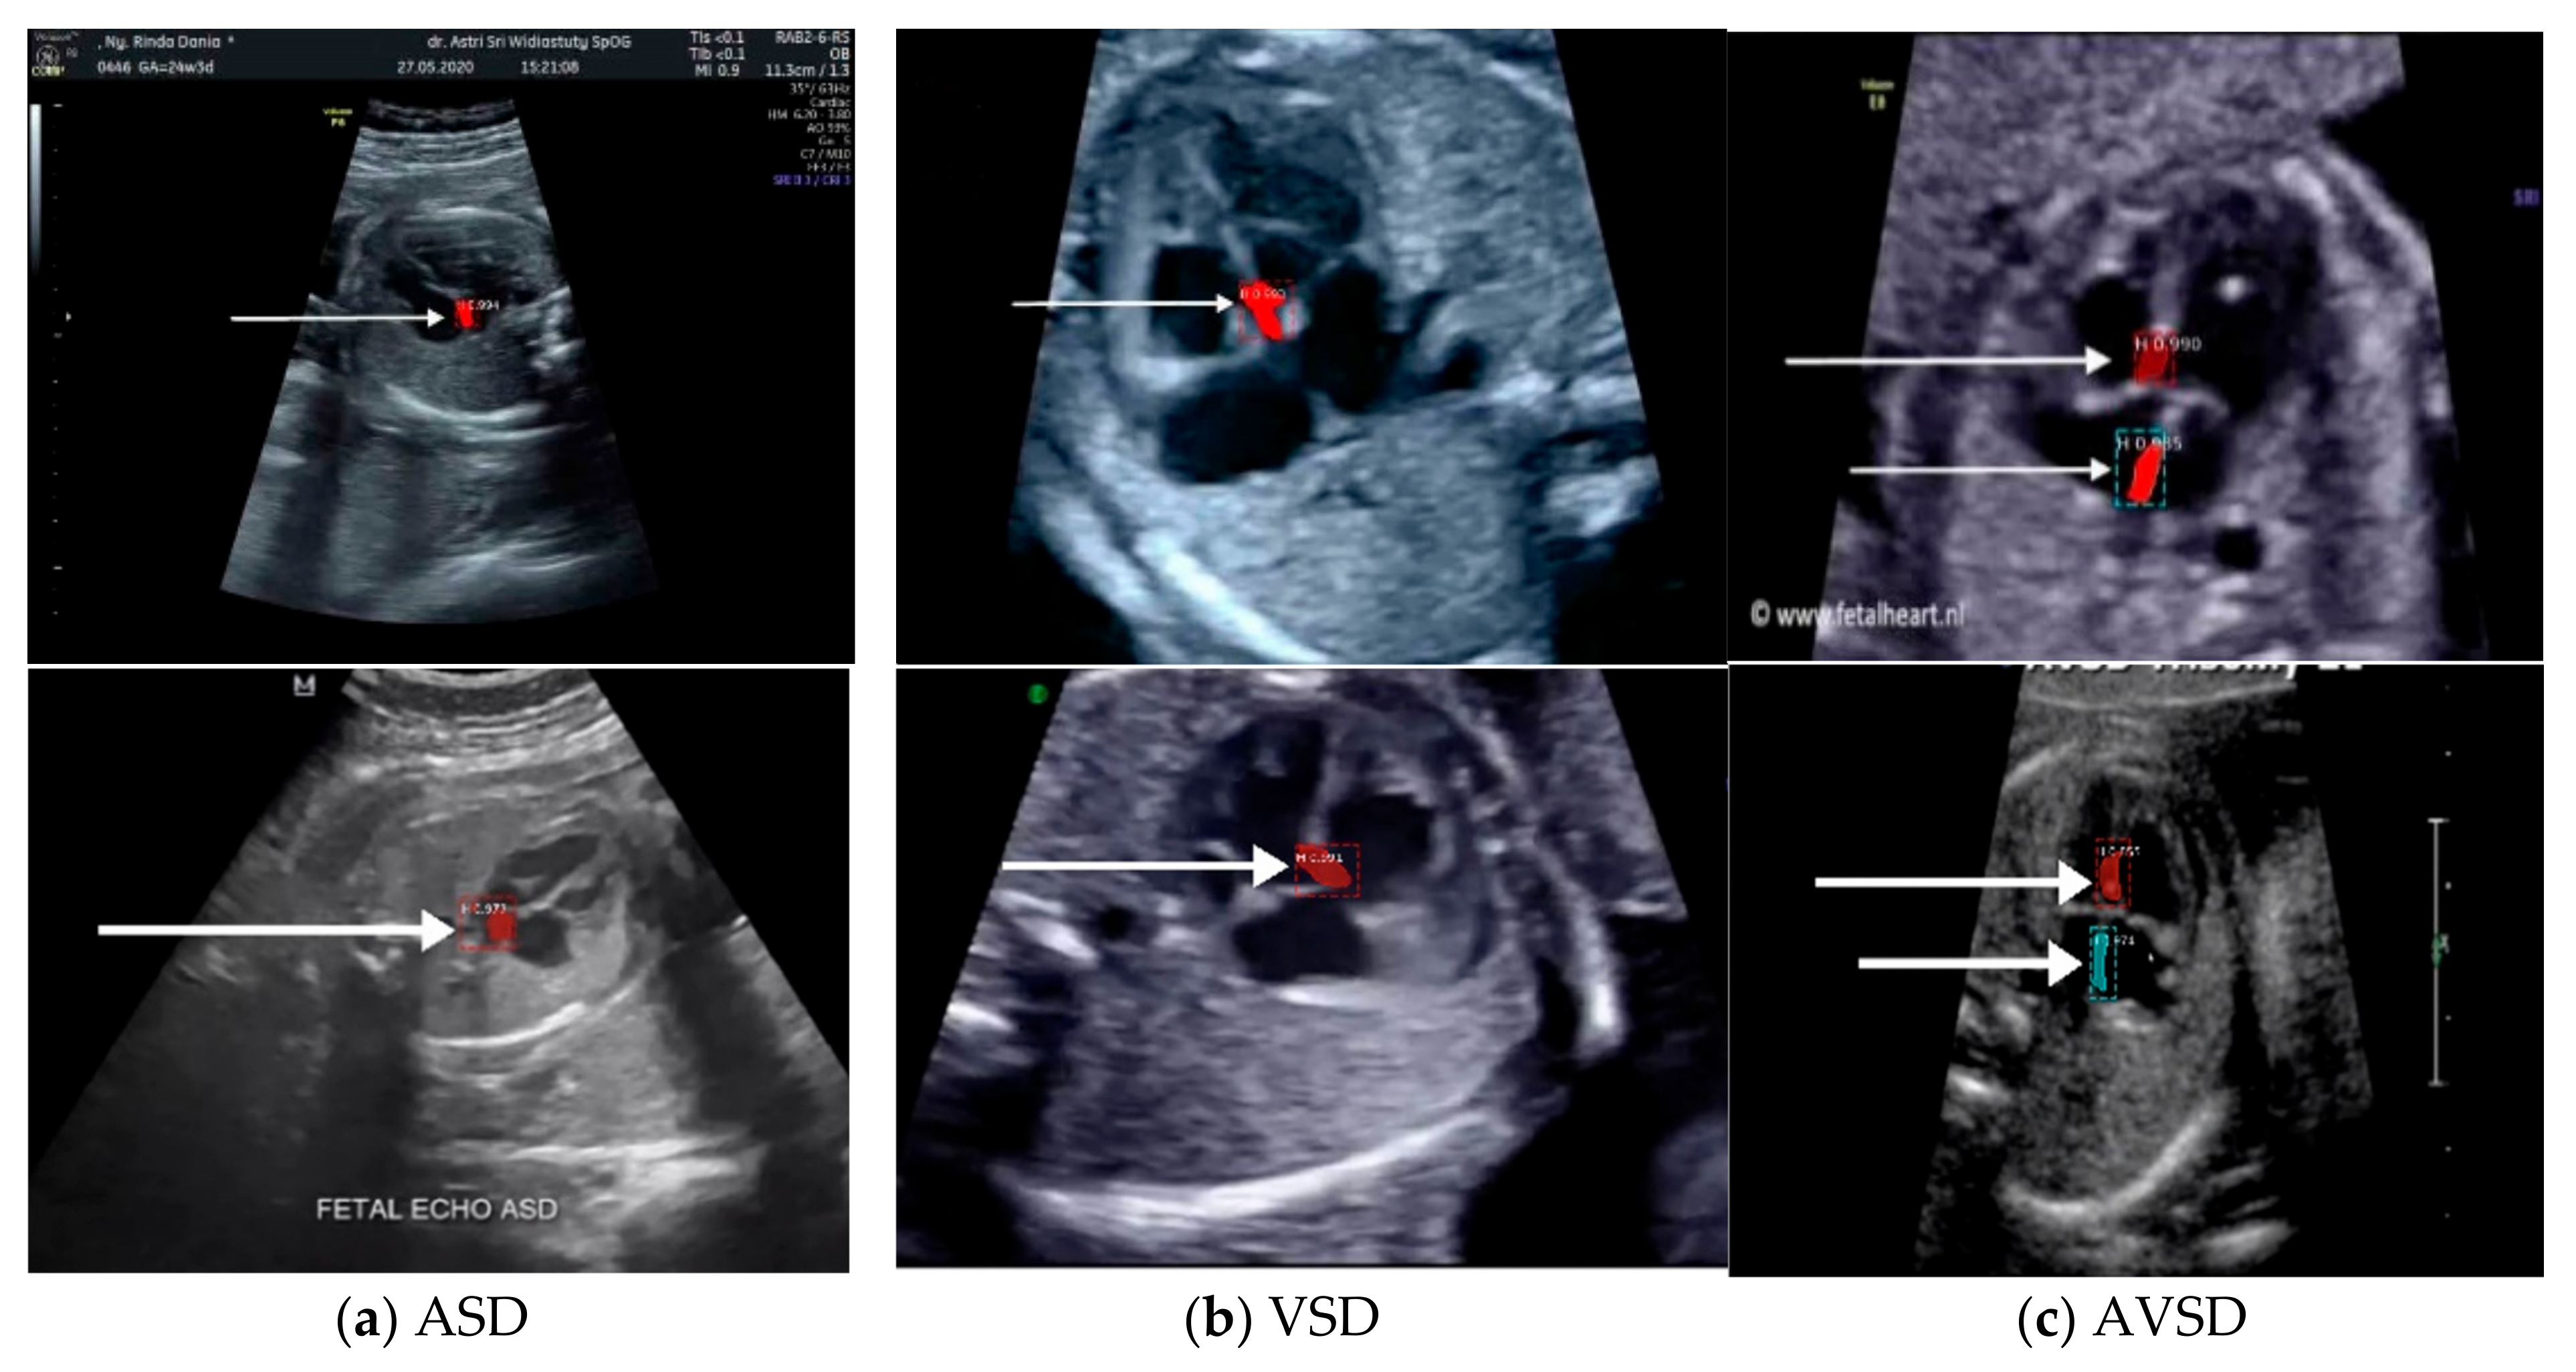

Images with inappropriate anatomical planes (cropped or badly captured) and those with calipers were excluded. The dataset composition was clearly imbalanced (some classes were more frequent than others), as is usually the case in real clinical scenarios. The sample of the raw ultrasound image was based on four views in normal anatomy, as depicted in Figure 2. In such sample, there are the left atrium (LA), left ventricle (LV), right atrium (RA), right ventricle (RV), ductus arteriosus (DUCT), superior vena cava (SVC), aorta ascendens (AoA), aorta descendens (Ao), and main pulmonary artery (MPA), whereas the sample of the raw ultrasound image of abnormal anatomy structure, with the three heart defects such as ASD, VSD, and AVSD condition, is compared to normal anatomy structure in Figure 3. In the abnormal structure, there are hole (H) as heart defect in each condition. Each defect has the variation of hole size; such hole size indicates the disease severity. However, in this study, we only detected the hole, without measuring the hole size.

Figure 3.

Fetal heart scan in 4CH view for CHDs detection: (a) ASD; (b) VSD; (c) AVSD; and (d) Normal.

The fetal heart anatomy in 4CH view showed the expected normal appearance [23]. As apical 4CH is the original gold standard view in fetal echocardiography, inability to image this should alert the scanner about a potential problem [24]. This view should not be mistaken for a simple chamber count as it involves a careful evaluation of specific criteria [24]. Based on such criteria, the detection of the fetal heart abnormality was screened only by 4CH view [8]. Three CHD conditions (with defects in atria, ventricles, and both) were measured with the IoU and DCS values. The minimum IoU value for detecting the defect object in each fetal heart was 0.5. High IoU and DCS values indicated that the defect prediction overlapped with the proposed architectural model, which is almost similar to the ground truth.

Two scenarios for the learning processes were conducted in this study based on intra- and inter-patient variation data. Intra-patient variations meant that a fetal heart image coming from the same patient was split for the testing process. Inter-patient variations meant that the tested fetal heart images were from different patients. In the intra-patient data for ASD, VSD, and AVSD, the proposed model produced IoU and DCS values exceeding 50%. However, for the inter-patient data, although a 55.99% IoU was obtained for ASD, the IoU values of VSD and AVSD were under 50%. The DCS value exceeded 50% for ASD and AVSD, but that of VSD was only close to 50% (refer to Table 5).

Overall, the defect detection performance reached over 50% in IoU and DCS for intra-patient data. The inter-patient data were hard to detect due to large variations in fetal heart images, size of defect, and image quality, especially in VSD and AVSD condition. The result was under 50% IoU; all measurement decreased about 13 to 15% if the proposed model was tested with unseen images.

The sample image of heart defect segmentation and detection is depicted in Figure 12. In the 18–21 weeks of pregnancy, the fetal heart has size around 24 mm [23], thus the hole (defect) size in the heart septum will have a size <24 mm. At this stage of development, therefore, it remains difficult to visualize with precision the details of cardiac anatomy as seen during fetal echocardiography. By using our proposed model, it can be segmented and detected with IoU and DCS about 59% and 69%, respectively, in intra-patient, and about 47% IoU and 57% DCS in inter-patient scenarios. This means our model has the ability to segment and detect until a 50% overlap with the ground truth.

Sample image result of CHDs detection with 4CH view. The white arrow indicates the defect, whereas red and blue colors are the defect position in the heart septum.

This study determined the mAP value for each defect condition (ASD, VSD, and AVSD) in addition to the IoU and DCS values. A high mAP value indicated that the defect prediction from the model was similar to the ground truth generated by the maternal–fetal consultant. Table 6 shows the object detection results with mAP performance; the highest mAP value (98.30%) was obtained from the intra-patient data; however, the mAP decreased to 82.42% in the inter-patient data. CNN-based instance segmentation works using a simple linear iterative clustering algorithm, which takes an image as input and outputs its division into super-pixels. The proposed model measures the overlap between the annotated input and predicted target, but it does not label all the image pixels, as it segments only the RoI. Therefore, if the input image is new (from inter-patient), the detection performance will decrease, but its performance still satisfactory due to the reduction only 16% with the mAP value over 80%.